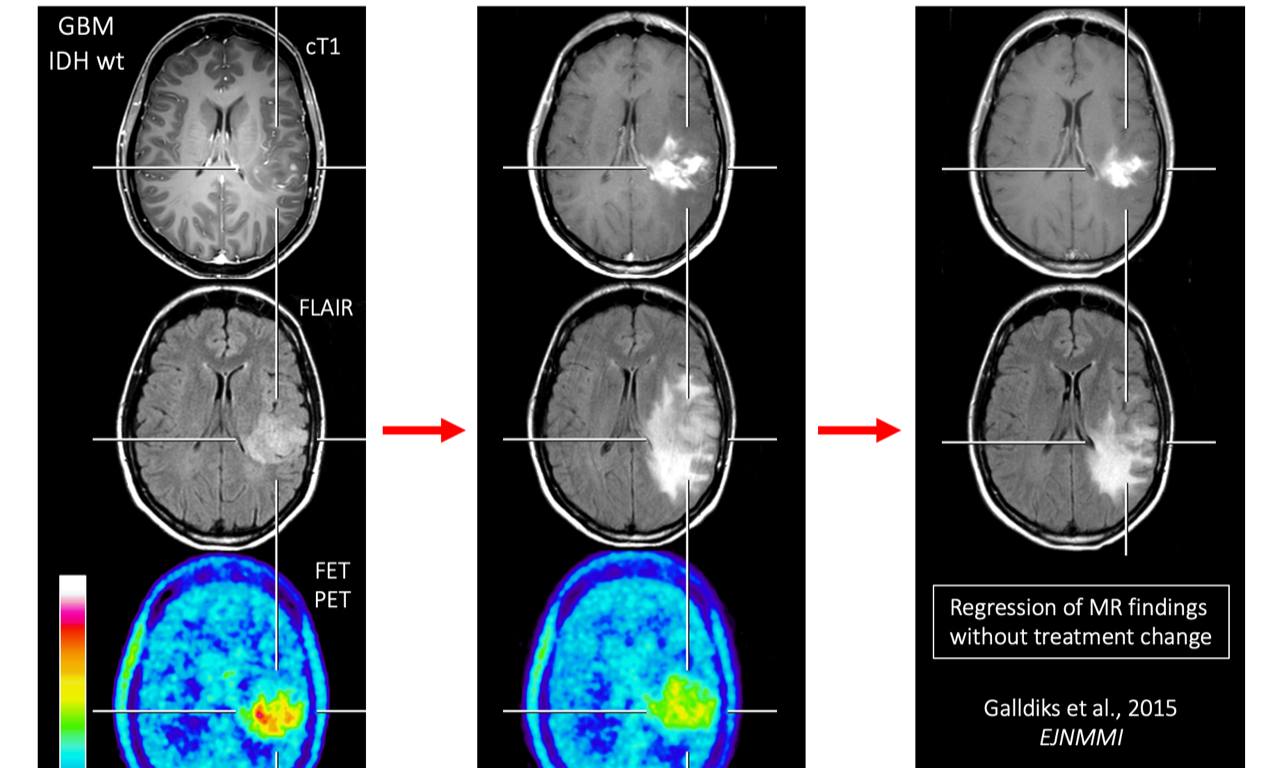

Mittels funktioneller Bildgebung (PET, MRT) werden systemische (neurale Netzwerke) und molekulare (Neurotransmission) Ansätze unter Einsatz mathematischer Modelle (z.B. dynamic causal modelling) zusammengeführt, um zu einem ganzheitlichen Verständnis der Entwicklung normaler Hirnfunktionen bei Gesunden als auch gestörter Hirnfunktionen bei neurologischen Patienten zu gelangen.